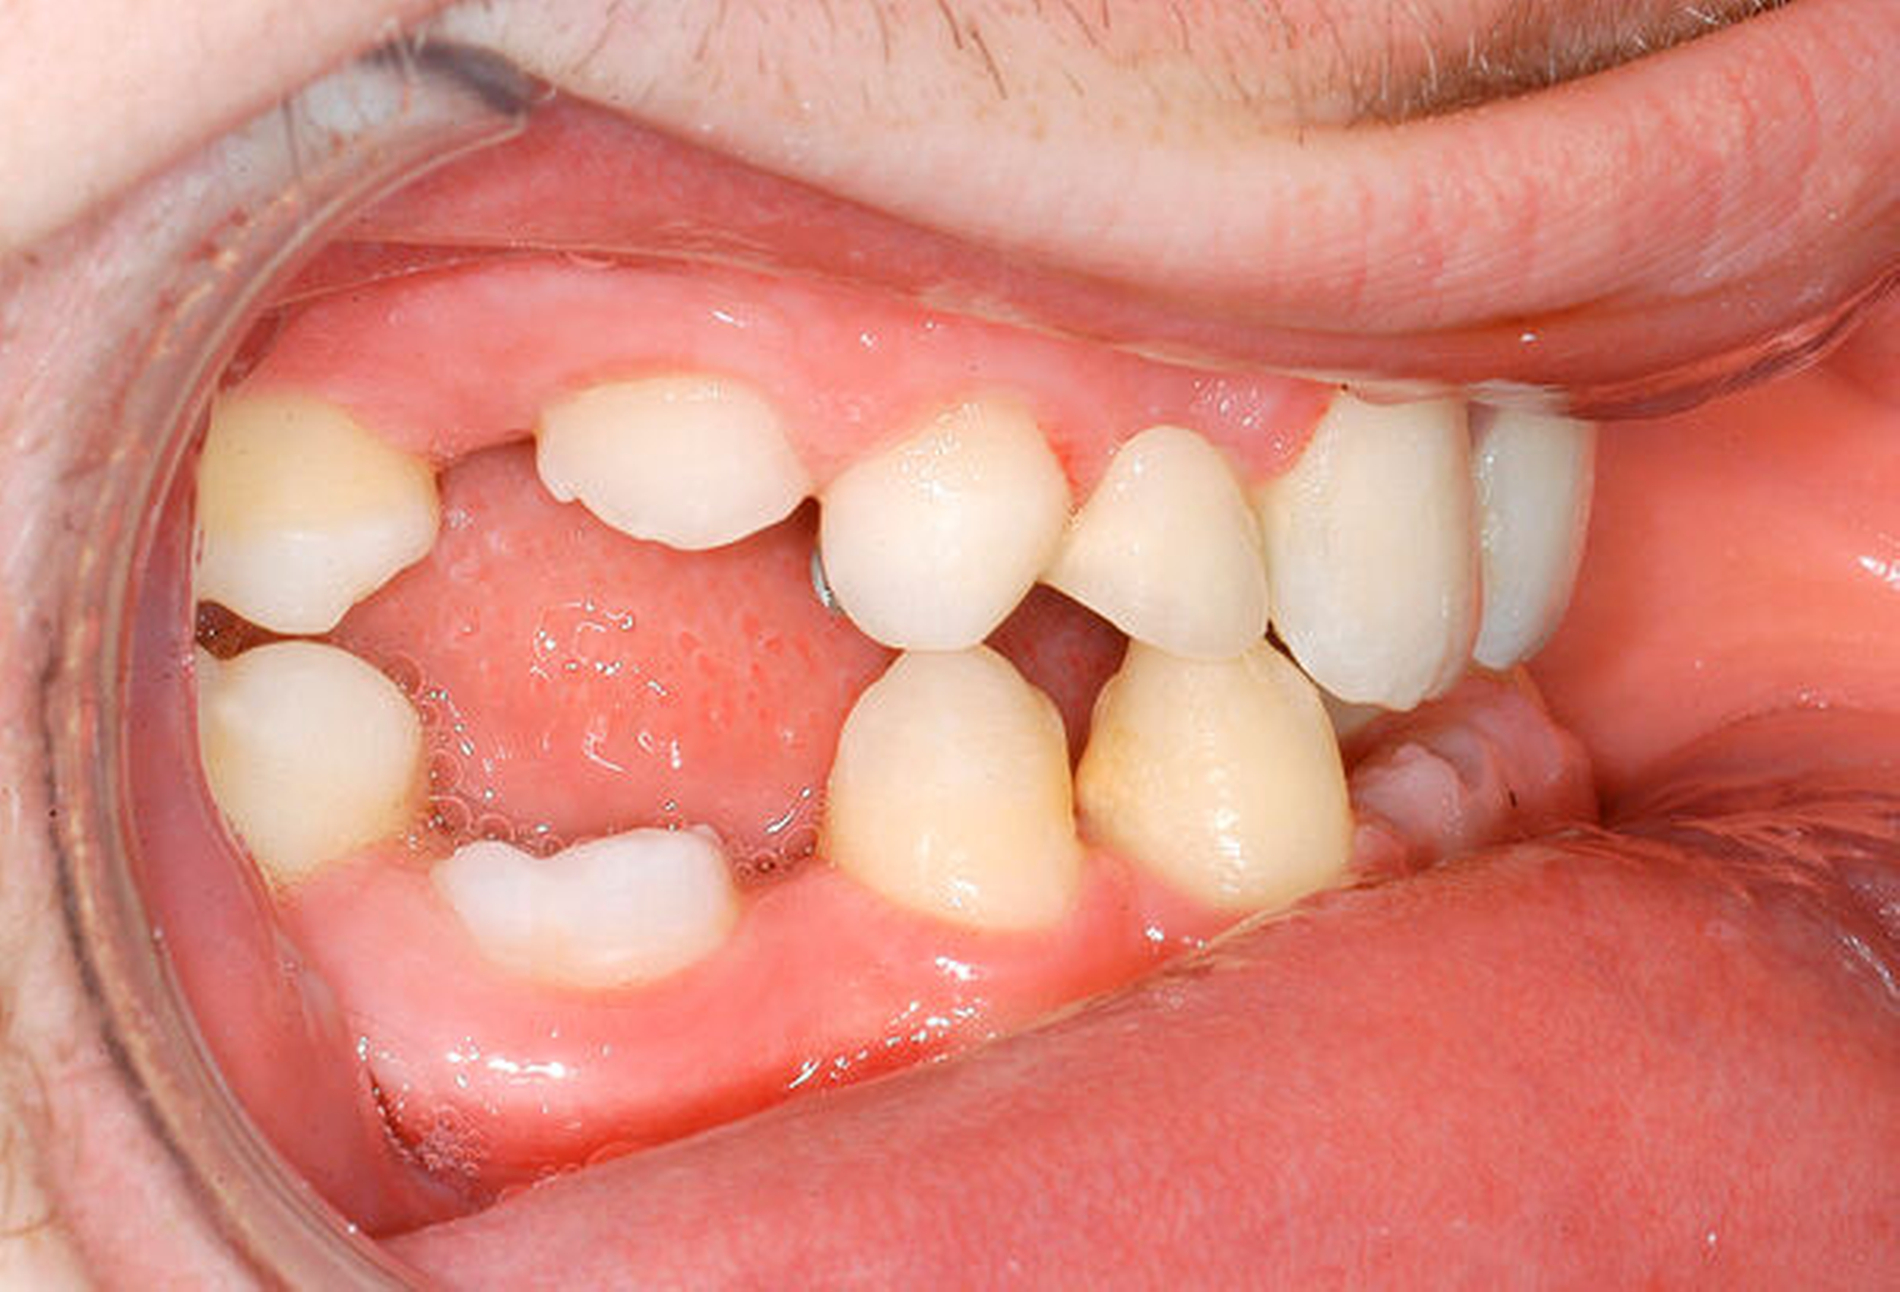

Beim intraoralen Befund imponierten neben multiplen Lücken ein partiell seitlich-offener Biss, eine auffällig konische Form der oberen mittleren Schneidezähne sowie persistierende Milchzähne (Abbildungen 2 bis 4). Zusammen mit der angefertigten Panoramaschichtaufnahme (Abbildung 5) konnte der Verdacht einer ausgeprägten Oligodontie bestätigt werden – insgesamt waren 22 Zähne inklusive der Weisheitszähne nicht angelegt. Auf Grundlage der bestehenden Befunde wurde der Verdacht einer genetischen Ursache der Symptome geäußert und dem Patienten zunächst eine molekulargenetische Abklärung mit der Verdachtsdiagnose „genetisch bedingte Zahnnichtanlagen / ektodermale Dysplasie“ empfohlen. Bei der Sequenzanalyse wurde eine Mutation im WNT10A-Gen nachgewiesen und somit die klinische Verdachtsdiagnose bestätigt.